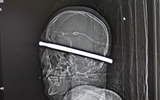

争分夺秒 挽救生命——兰大二院急诊ICU成功救治一名钢筋贯通患者